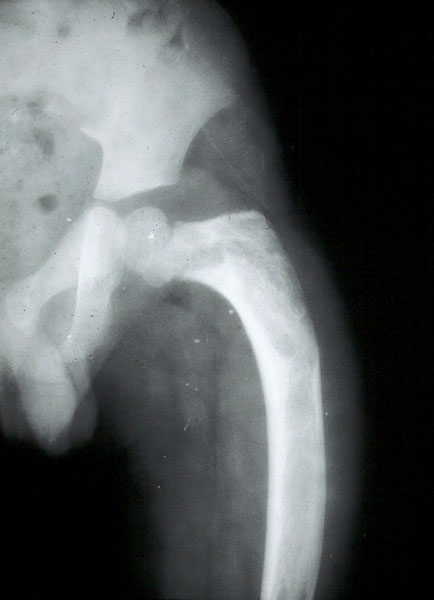

In the pelvis, proximal ends of the femura are commonly involved. Generally it is unilateral (Figure 16). In polyostotic form, involvement of the iliac and other bones is common (Figure 17). Radiologically, the head and neck of the femur are deformed and present a shepherd’s crook deformity (Figure. 18). On occasion, a cystic lesion with multiple loculations is encountered (Figure 19).

Shafts of femur, tibia, fibula etc., show expanding lesion with a thick rind. Ground glass appearance of the matrix is the hall mark for diagnosis (Figures 20a,b,c & 21a,b).

Figure 20: FD – (a,b) Mid shaft of femur simulating aneurysmal bone cyst, (c) post operative.

Figure 21a,b: FD tibia – incidentally found when investigating for trauma.